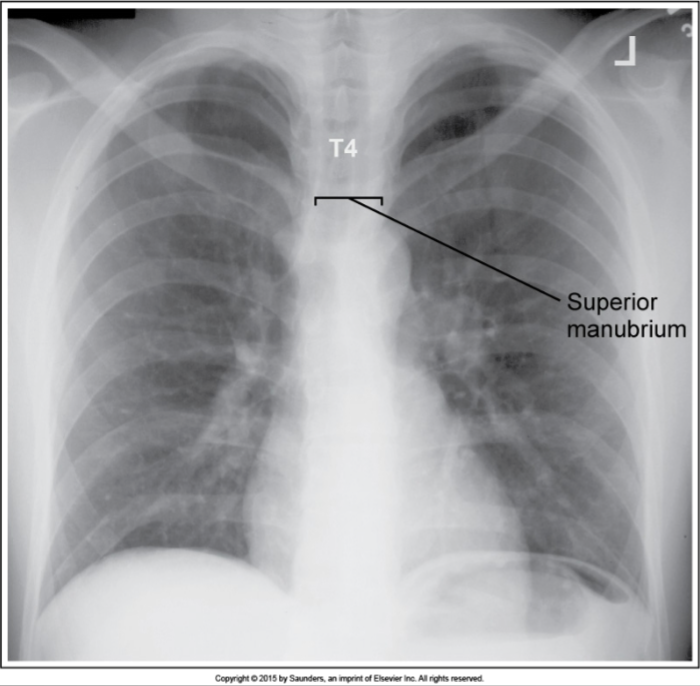

PA Chest

inaccurate image

superior MCP tilted posteriorly